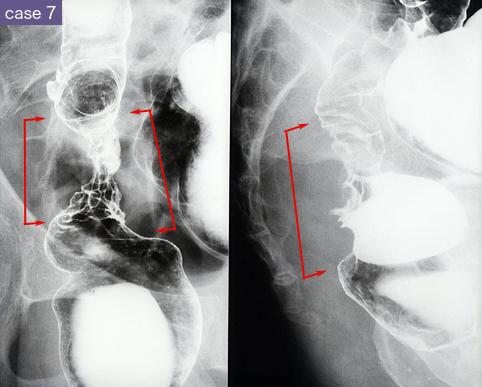

Radiographic pictures of nine cases of recurrent colorectal cancer which developed in the anastomotic area.

Malignant epithelial tumor/Adenocarcinoma

Location

Large intestine(Colon)/Sigmoid colon

X-ray

40 -